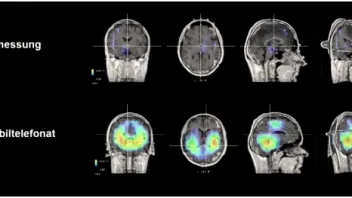

Das gut einstündige Interview mit den beiden Forschern zeigt so manche neue Erkenntnis, die erschreckend ist. Verdeutlicht werden die Aussagen anhand von neuartigen 3D-EEG-Aufnahmen, auf denen erstmals auch für Laien ersichtlich wird, wie tief (räumlich gesehen) die Strahlungen ins Gehirn eindringen und dadurch auch Schäden auf Mitochondrienebene stattfinden können und auch der Hypothalamus betroffen ist.